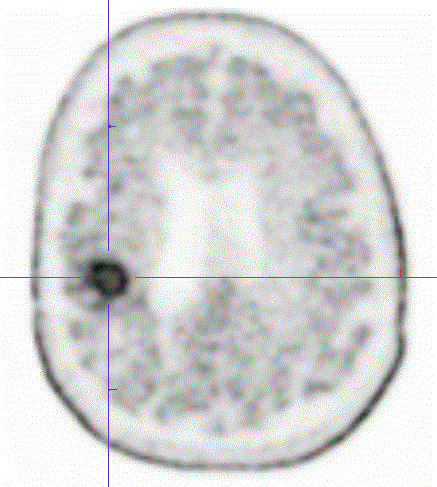

Ukázka vyšetření

Transverzální řez mozkem u pacienta s pozvolnou progresí MRS nálezu a MR sycení a v pravém parietálním operkulu 10 let po operaci gangliogliomu gr. I a po radioterapii před 5 lety. Ložiskové nakupení radiofarmaka v uváděné lokalitě s fotopenickým centrem s vysokou pravděpodobností svědčí pro přítomnost viabilní neoplazie s centrální nekrózou.